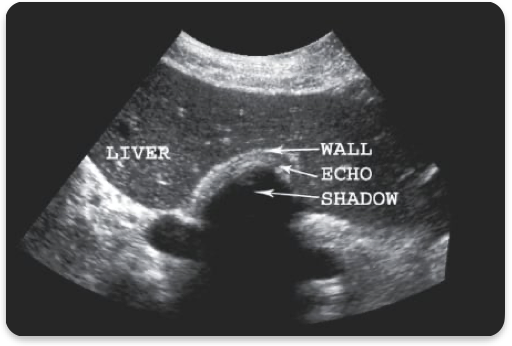

WES sign

GB completely filled w/ stones. Only anterior wall visualized

Cholelithiasis, gallstones